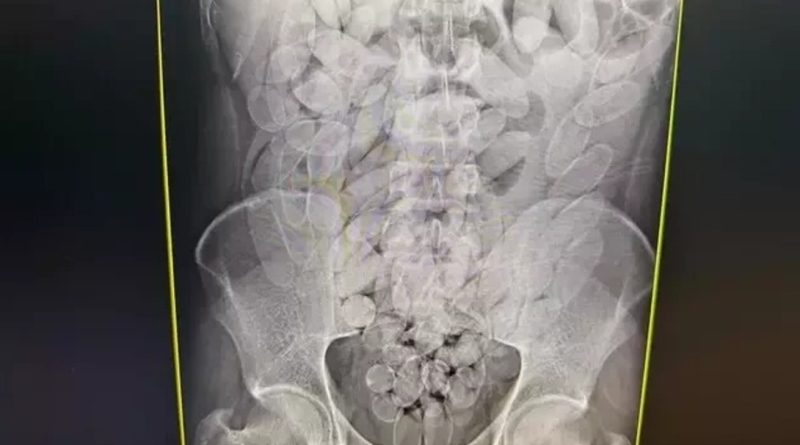

Os raios X mostraram que os oito haviam engolido cápsulas de pasta base de cocaína. A droga foi retirada de forma segura por equipe médica, totalizando 645 cápsulas, publicou o Dourados Informa. Após o procedimento, todos foram encaminhados à PF (Polícia Federal), onde permanecem à disposição da Justiça.